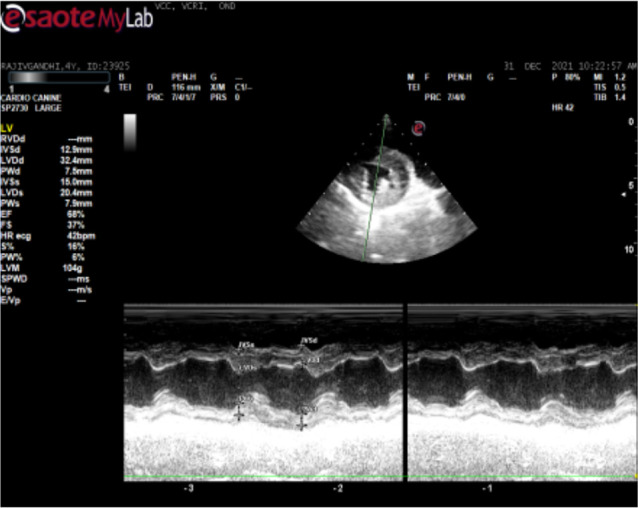

锥虫是红细胞外的血鞭毛原虫,寄生于包括狗在内的家养和野生动物体内。一只雄性罗威纳犬因厌食、眼睛浑浊和呕吐一周而就诊。对该犬进行了身体和临床检查。采集了血液并进行了血液学和生化分析。进行了胸腔超声心动图和腹腔超声波检查。通过 PCR 对寄生虫进行了分子确认,并对 DNA 进行了测序,以确定菌株变异。经临床检查,该犬消瘦,伴有高烧、单侧角膜混浊、贫血、淋巴结肿大和腹部膨胀。胸腔超声心动图显示心室肥大和心肌病。腹腔超声波检查显示脾脏肿大和肾脏肿大。血液学检查结果显示血红蛋白和红细胞计数下降,生化检查结果显示尿素氮和肌酐升高、低血糖和低白蛋白血症。湿片和血涂片检查分别显示锥虫运动活跃和锥虫大量感染。通过扩增 evansi 锥虫的 227 bp 部分 VSG 基因进行了分子鉴定,随后进行了测序和系统发育分析。感染犬在接受支持疗法的同时,肌肉注射醋酸地米那嗪(3.5 毫克/千克体重)。该研究描述了犬锥虫病的发生和诊断。早期诊断和及时治疗是保护伴侣动物的最可靠方法。这是印度泰米尔纳德邦考弗里三角洲地区首次报告犬锥虫病。

Trypanosomes are the extraerythrocytic haemoflagellate protozoan parasites of domestic and wild animals including dogs. A male Rottweiler dog was presented with the history of anorexia, cloudy eyes and vomiting for a week. The dog was examined both physically and clinically. Blood was collected and subjected to haematological and biochemical analysis. Echocardiography of the thoracic cavity and ultrasonography of the abdominal cavity were performed. Molecular confirmation of parasite was carried out by PCR and DNA was sequenced to identify strain variations. Upon clinical examination, the dog revealed emaciation with high fever, unilateral corneal opacity, anemia, enlarged lymph nodes and distended abdomen. Echocardiography of the thoracic cavity showed ventricular hypertrophy and cardiomyopathy. Ultrasonography of the abdominal cavity showed splenomegaly and renomegaly. Haematological findings revealed decreased haemoglobin and erythrocyte count and biochemical findings revealed increased BUN and creatinine, hypoglycemia and hypoalbuminemia. Wet film and blood smear examination revealed actively motile trypanosomes and massive infection of trypanosomes, respectively. Molecular confirmation of species was carried out by amplification of 227 bp partial VSG gene of Trypanososma evansi, subsequently sequenced and phylogenitically analysed. The infected dog was treated intramuscularly with diminazene aceturate @ 3.5 mg/kg b.wt along with the supportive therapy. The study described the occurrence and diagnosis of trypanosomosis in dog. Early diagnosis and timely treatment is the most reliable way to safeguard the companion animals. It is the first report on trypanosomosis in dog from Cauvery delta region of Tamil Nadu, India.